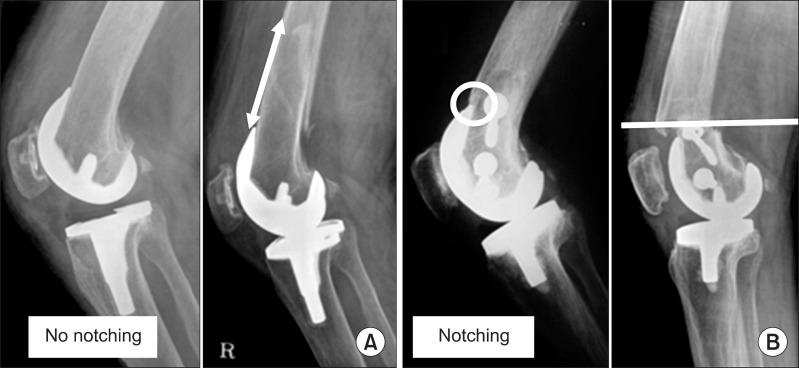

全膝关节置换术后假体周围股骨远端骨折的微创钢板接骨术

Minimally invasive plate osteosynthesis for periprosthetic distal femoral fractures after total knee arthroplasty.

To evaluate the outcomes of the treatment of distal femoral fractures using minimally invasive plate osteosynthesis following total knee arthroplasty (TKA).

From July 2008 to October 2011, 14 patients were treated with minimally invasive plate osteosynthesis for periprosthetic fractures following TKA. The mean duration of follow-up was 19.2 months and the mean age was 69.7 years. Lewis and Rorabeck classification was used to categorize the type of fracture. Pre- and postoperative range of motion, femorotibial angle, and Knee society score, time to bony union, and complications were evaluated.

The mean range of motion was 108.4 degrees preoperatively and 107.3 degrees postoperatively. No significant difference was observed in the pre- and postoperative mean range of motion. The average time to bony union was 3.9 months. The knee society score was 82.6 points preoperatively and 78.9 points postoperatively. The mean femorotibial angle was changed from 6.1 degrees valgus postoperatively to 4.6 degrees valgus postoperatively. There was no complication during the follow-up.

Minimally invasive plate fixation for distal femur fractures after TKA showed good results. Minimally invasive plate osteosynthesis is a recommendable treatment method for periprosthetic fractures.